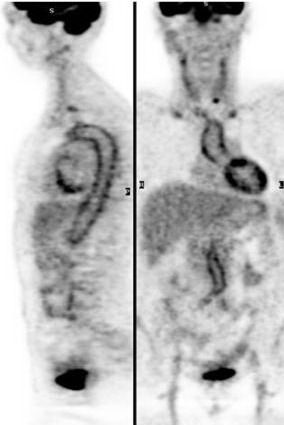

PET và PET/CT có tác dụng đặc biệt đối với ung thư. Các phương pháp chẩn đoán hình ảnh như chụp cắt lớp vi tính (CT), cộng hưởng từ (MRI), siêu âm... chỉ phát hiện và đánh giá được các tổn thương đã có những thay đổi về cấu trúc, giải phẫu, mật độ của tổ chức. Vì vậy các phương pháp này thường gặp khó khăn hoặc dễ bỏ sót các tổn thương có đường kính < 1cm. Trong khi đó chụp hình toàn thân bằng PET và PET/CT có thể phát hiện các bất thường về chuyển hoá, ghi được những hình ảnh bệnh lý sớm, còn nhỏ khi chưa có thay đổi cấu trúc. Ở các bệnh nhân ung thư, sau phẫu trị, xạ trị, hoá trị các tổn thương có thể bị biến dạng, thay đổi cấu trúc nên hình ảnh CT, MRI có nhiều hạn chế trong việc xác định tổ chức còn sót, không phân biệt được tổ chức xơ hoá với tái phát, di căn... Kỹ thuật PET cho phép khắc phục nhược điểm đó của CT và MRI. Vì vậy độ nhạy, độ đặc hiệu để chẩn đoán ung thư của PET cao hơn rất nhiều các phương pháp chẩn đoán hình ảnh khác. Do vậy hiệu quả kinh tế, xã hội của PET và PET/CT là rất rõ rệt.

4. Ghi hình khối u bằng máy PET (Ghi hình khối u theo nguyên tắc chuyển hoá) và PET/CT- Ứng dụng đặc biệt quan trọng của PET là phát hiện khối u ung thư cũng như theo dõi sự tái phát ung thư, đánh giá kết quả của các phương pháp điều trị. Nếu như CT, MRT cung cấp hình ảnh giải phẫu rõ nét thì PET vừa cho chúng ta hình ảnh giải phẫu vừa cho hình ảnh chức năng chuyển hoá của khối u. Do vậy, nhìn chung ghi hình khối u bằng PET có độ nhạy và độ đặc hiệu cao hơn nhiều so với các phơng pháp chẩn đoán hình ảnh khác, đặc biệt là khả năng phát hiện các khối u ở giai đoạn rất sớm khi mà các phơng pháp chẩn đoán khác chưa phát hiện thấy.

Về mặt kỹ thuật PET có thể ghi lại và tái tạo ảnh theo 3 chiều không gian. Độ dày một lớp cắt khoảng 3 - 4mm và có thể cắt theo 3 chiều (nằm ngang, chiều đứng trước - sau và phải - trái). Đặc biệt PET có thể ghi hình toàn thân hoặc từng phần cơ thể.